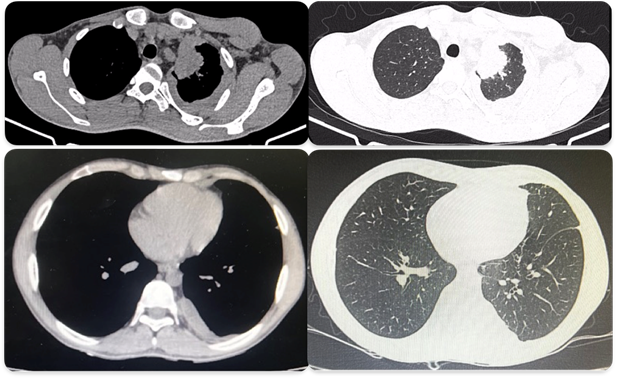

O paciente foi transferido ao Hospital Universitário Getúlio Vargas para investigação diagnóstica. A TC de tórax com contraste confirmou um pequeno derrame pleural à esquerda, associado a espessamento pleural difuso e irregular, com realce heterogêneo pelo meio de contraste e formações nodulares intercaladas, a maior medindo 0,9 cm. Identificaram-se múltiplas linfonodomegalias mediastinais e hilares de tamanhos variados, com centro hipodenso, sendo a maior localizada na janela aorta-pulmonar, medindo 1,6 cm. Consolidações com vidro fosco foram observadas no segmento apico-posterior do lobo superior esquerdo e inferior esquerdo, além de uma formação lobulada heterogênea, com captação intensa pelo contraste e áreas de degeneração cística/necrótica, localizada no aspecto medial da região apical esquerda, em íntimo contato com a artéria subclávia esquerda, levantando alta suspeita de envolvimento neoplásico (Figura 1A).

Embora as culturas e o teste rápido molecular tenham sido negativos para Mycobacterium tuberculosis (MTB), o contexto clínico e epidemiológico, combinado com os achados histológicos, levou ao diagnóstico de tuberculose pleural. O tratamento com esquema básico para tuberculose (2RHZE/4RH) foi iniciado, resultando em melhora clínica completa sem efeitos adversos. Após seis meses de terapia medicamentosa, uma nova TC de tórax mostrou resolução significativa do espessamento pleural e das alterações previamente descritas (Figura 1B).